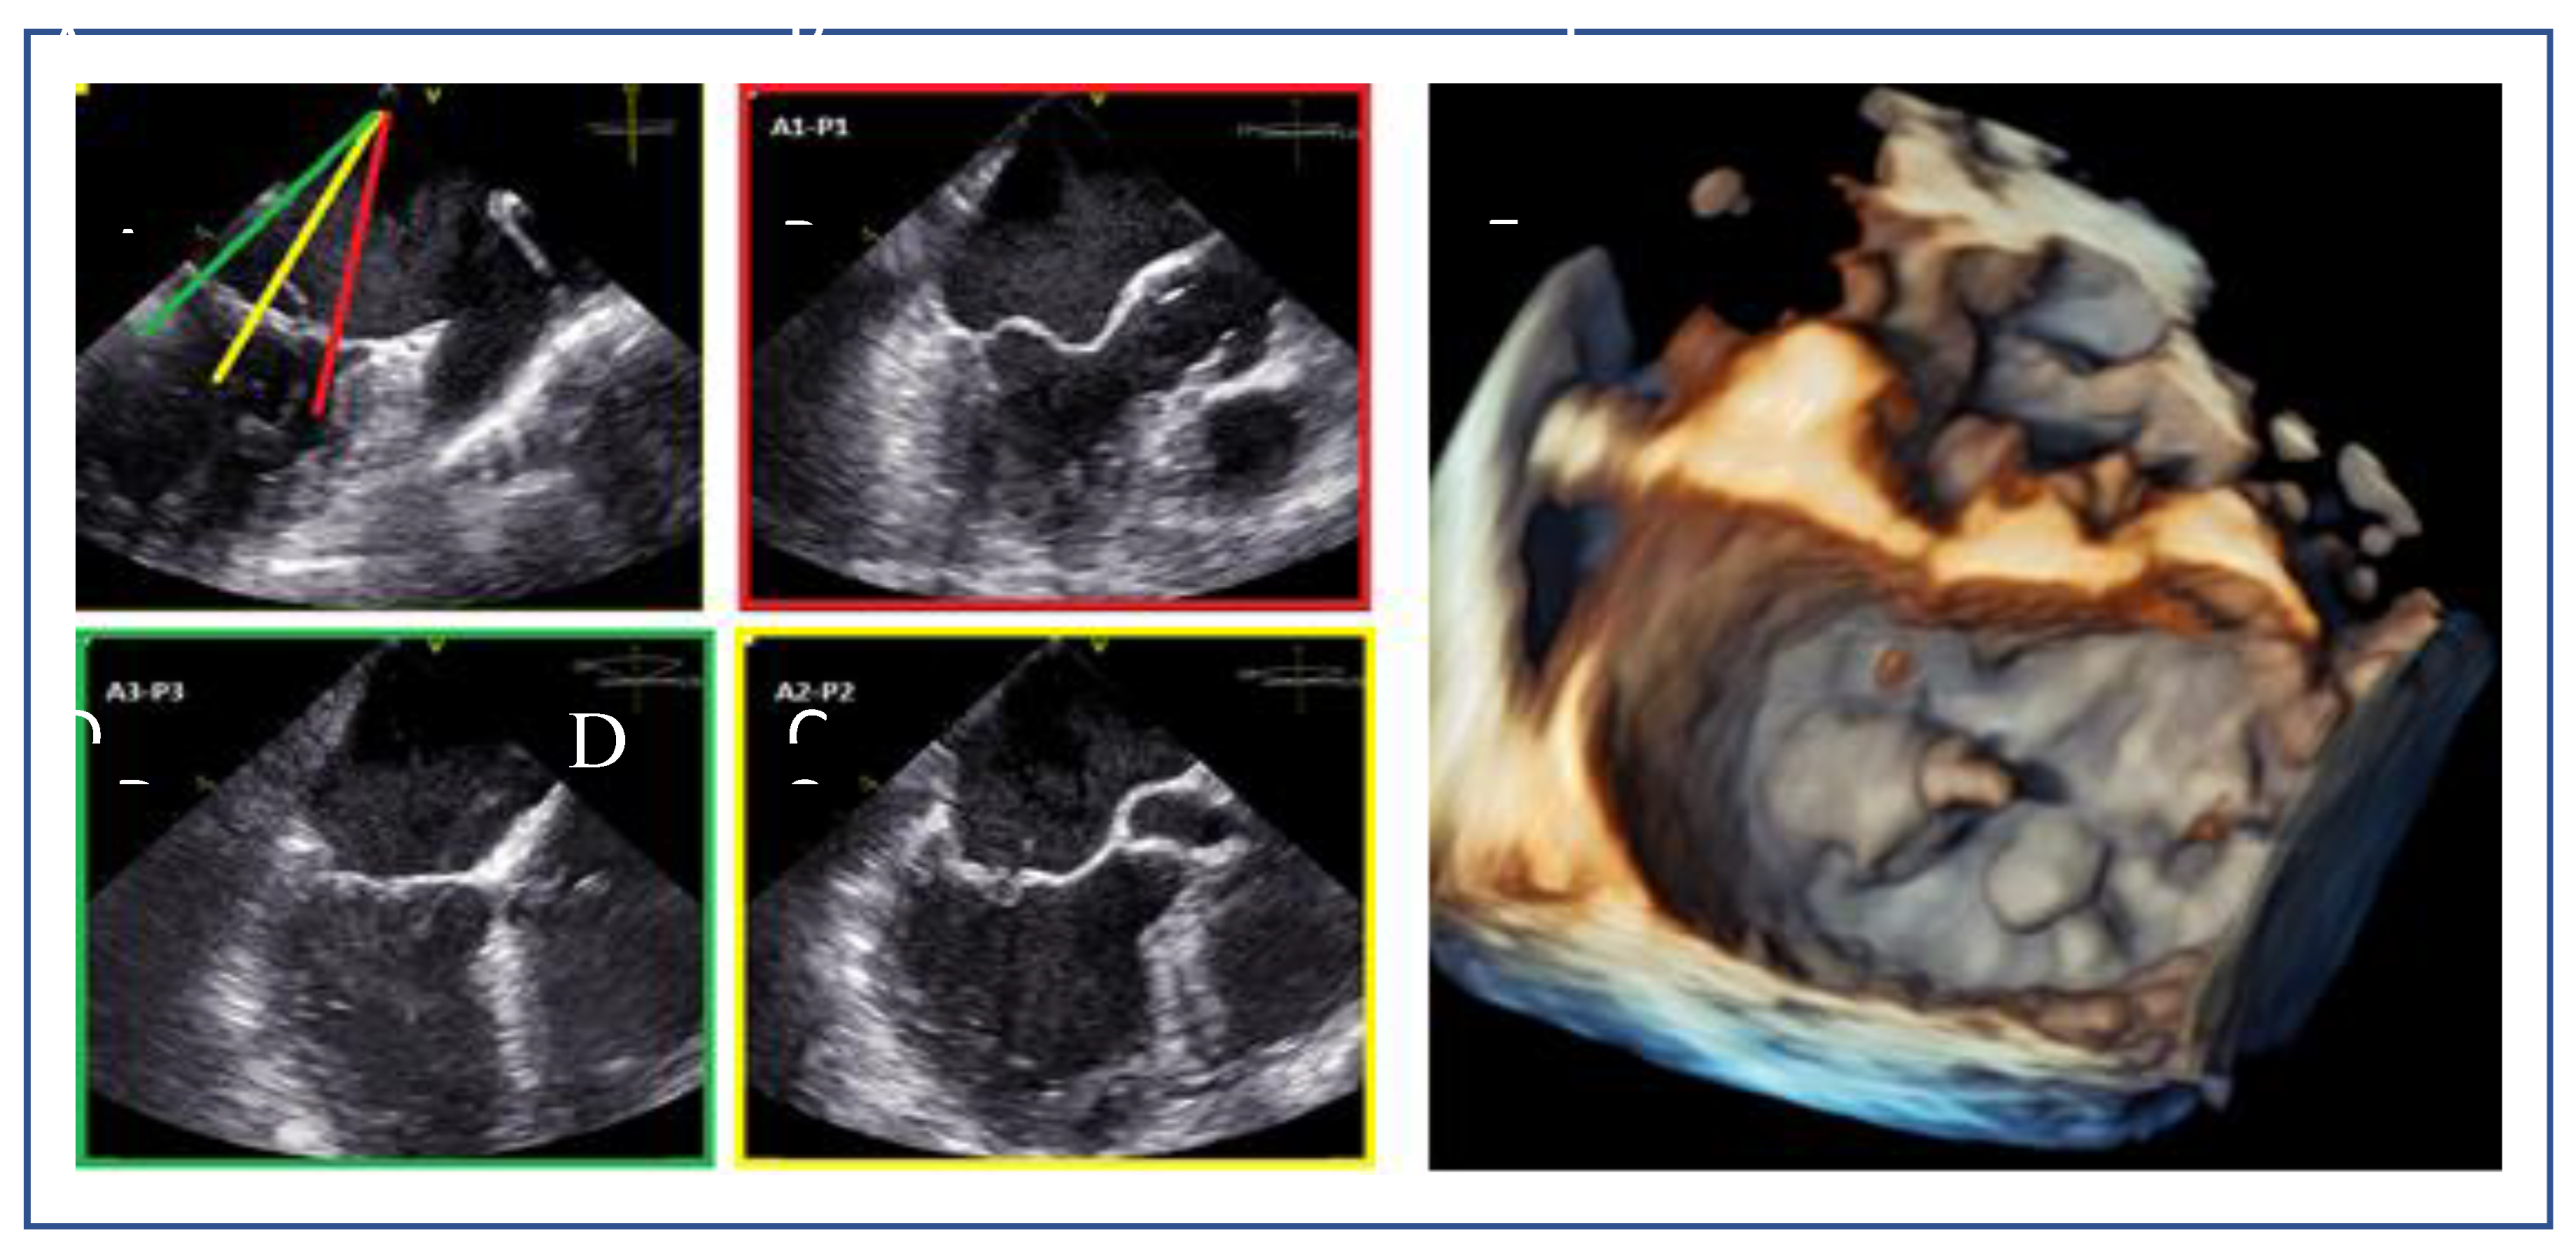

Posterior Leaflet Cleft-like IndentationThe posterior leaflet normally has two indentations that differentiate the scallops. A cleft-like indentation is defined as having a depth of at least 50% of the adjacent scallops [37,38] and 3D imaging is the best option to recognize such abnormalities (Figure 9). This feature makes grasping challenging and may lead to residual mitral regurgitation (MR).